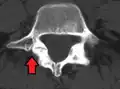

Anterolistesis L5/S1. Flecha azul pars interarticularis normal. La flecha roja es una ruptura en pars interarticularis -

Anterolistesis L5/S1